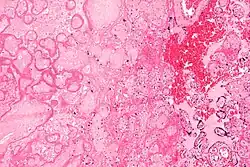

| Micrograph of a placental infarct (left of image), a cause of intrauterine hypoxia. H&E stain. | |